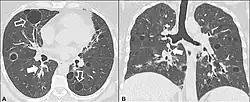

In the lungs, emphysema involves enlargement of the distal airspaces,[2] and is a major feature of chronic obstructive pulmonary disease (COPD). Other pneumatoses in the lungs are focal (localized) blebs and bullae, pulmonary cysts and cavities.

Lung cysts

A lung cyst, or pulmonary cyst, encloses a small volume of air, and has a wall thickness of up to 4 mm.[3] A minimum wall thickness of 1 mm has been suggested,[3] but thin-walled pockets may be included in the definition as well.[4] Pulmonary cysts are not associated with either smoking or emphysema.[5]